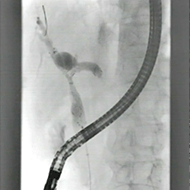

肝門部胆管癌に対する両葉金属ステント

膵癌による十二指腸狭窄に対する十二指腸ステント+胆管ステント